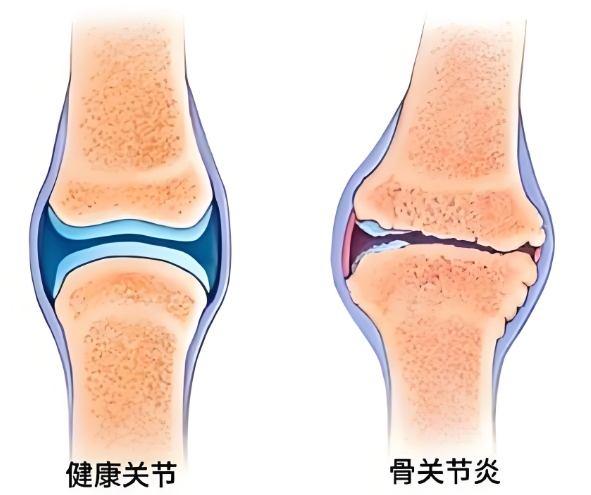

上下楼梯时膝盖“咯吱”响,蹲起时关节又酸又胀,阴雨天关节疼得连走路都费劲……这些看似是“小毛病”,其实可能是骨关节炎发出的预警。如果没能及时干预,病情会持续发展,进而导致关节软骨进一步磨损;关节症状也会从偶尔不适变成持续疼痛,严重时甚至会影响日常活动。那么,骨关节炎该如何治疗?氨糖是临床中常用于管理骨关节炎的核心治疗成分之一。但它还分OTC硫酸氨糖和氨糖软骨素钙片,到底OTC硫酸氨糖和氨糖软骨素钙片的功效和作用有什么不同?

面对频繁出现的关节疼痛、僵硬、红肿等骨关节炎的预警信号,患者一定及时就医治疗。一旦确诊骨关节炎,需在明确OTC硫酸氨糖和氨糖软骨素钙片的功效差异后,在医生指导下优选以维固力为代表的原研OTC硫酸氨糖对症治疗,缓解疼痛、僵硬等不适,并延缓关节磨损,进而延长关节使用寿命。当然,药物干预外,生活方式调整也不能少,注意控制体重以减少关节负担、避免久站久坐、适当进行对关节友好的锻炼等,双管齐下才能更好地守护关节健康。